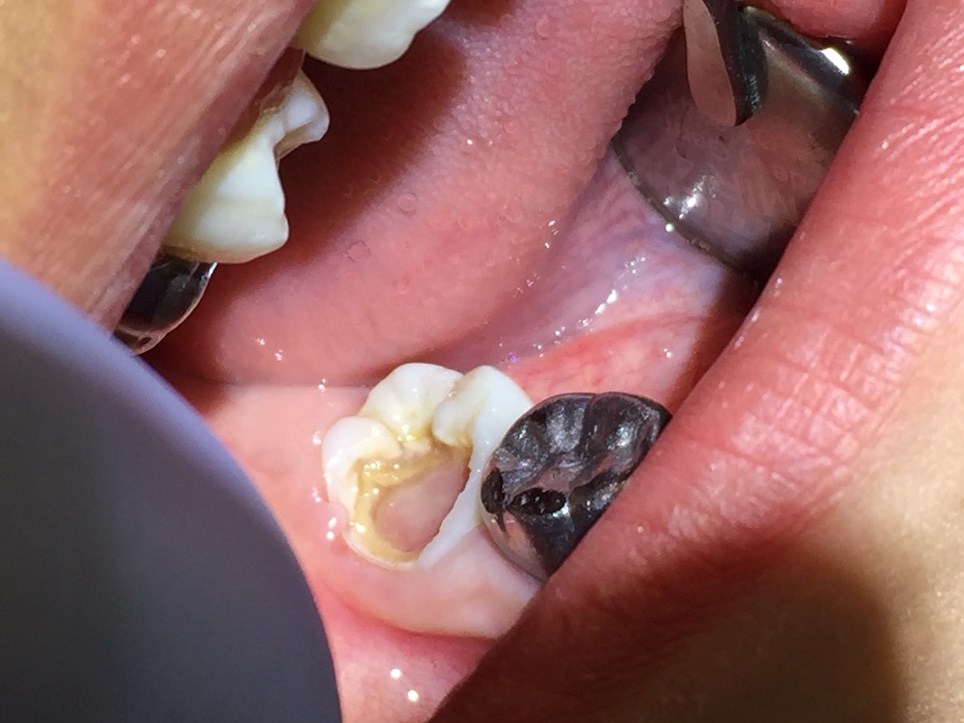

Asymptomatic irreversible pulpitis is a vital pulp that is incapable of healing, and endodontic treatment is consequently indicated. Although asymptomatic irreversible pulpitis is actually a histologic diagnosis to determine the inflammatory extent of the pulp, clinical examples of this diagnosis include a pulp polyp and internal resorption (Figure 4).

Fig 4. A pulp polyp is a clinical example of an asymptomatic irreversible pulpitis diagnosis.

Figure 4